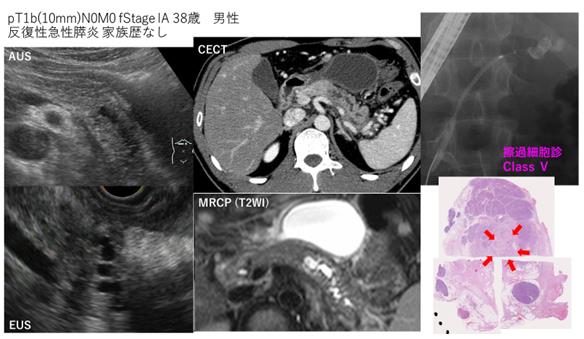

该患者因反复发生急性胰腺炎而被怀疑患有胰腺癌,我被送往医院。检查显示胰腺中的肿瘤为10mm,胰管也扩张。

可以从胰腺尾部的胰管扩张中发现胰腺癌

具体而言,我们通过CT / MRCP /超声波内窥镜等定期确定残留的胰腺是否有肿块,胰管扩张等。